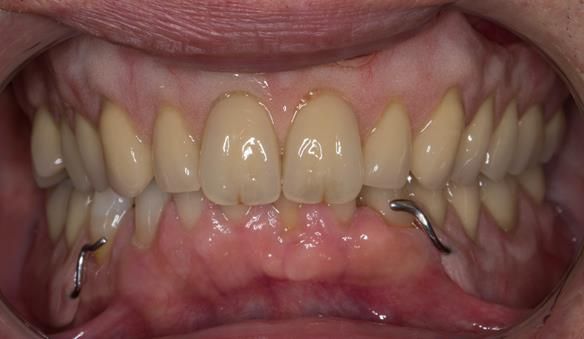

This 52 year old man was referred to me from his general dental practitioner in 2018.

10 years prior to consultation the patient's general dentist diagnosed periodontitis and referred him to Manchester Dental Hospital. He received a treatment plan to manage the periodontitis. Unfortunately, this was not acted on. Four years ago gaps developed between the upper front teeth. Orthodontic treatment was provided to align the teeth. A bonded retainer was fitted onto the upper front teeth. Approximately one year prior to consultation with me the patient noticed the teeth moving again. He consulted his orthodontist, who advised no further orthodontic treatment. One month prior to the consultation with me the upper left central incisor fell out whilst eating.

- Generalised periodontitis; stage IV grade C: currently unstable, risk factors: smoker.

- The remaining maxillary teeth had hopeless prognosis in the short term. They exhibited 80 - 100% alveolar bone loss with increased mobility (Grade 2 - 3).

The clinical situation and treatment process is shown in detail below with photographs.